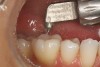

Another preparation technique is the use of air abrasion to remove the area of decay. Figure 1 shows tooth No. 19 with a sealant restoration. Using the Diagnodent, recurrent decay was detected. An air abrasion system was used to remove the old sealant restoration as well as the recurrent decay without the need for local anesthetic (Figure 2). The use of air abrasion allows for the efficient removal of the old resin material as well as the removal of the carious tooth structure.

Figure 2  Air abrasion is used to remove the old restoration and recurrent decay.

Figure 2